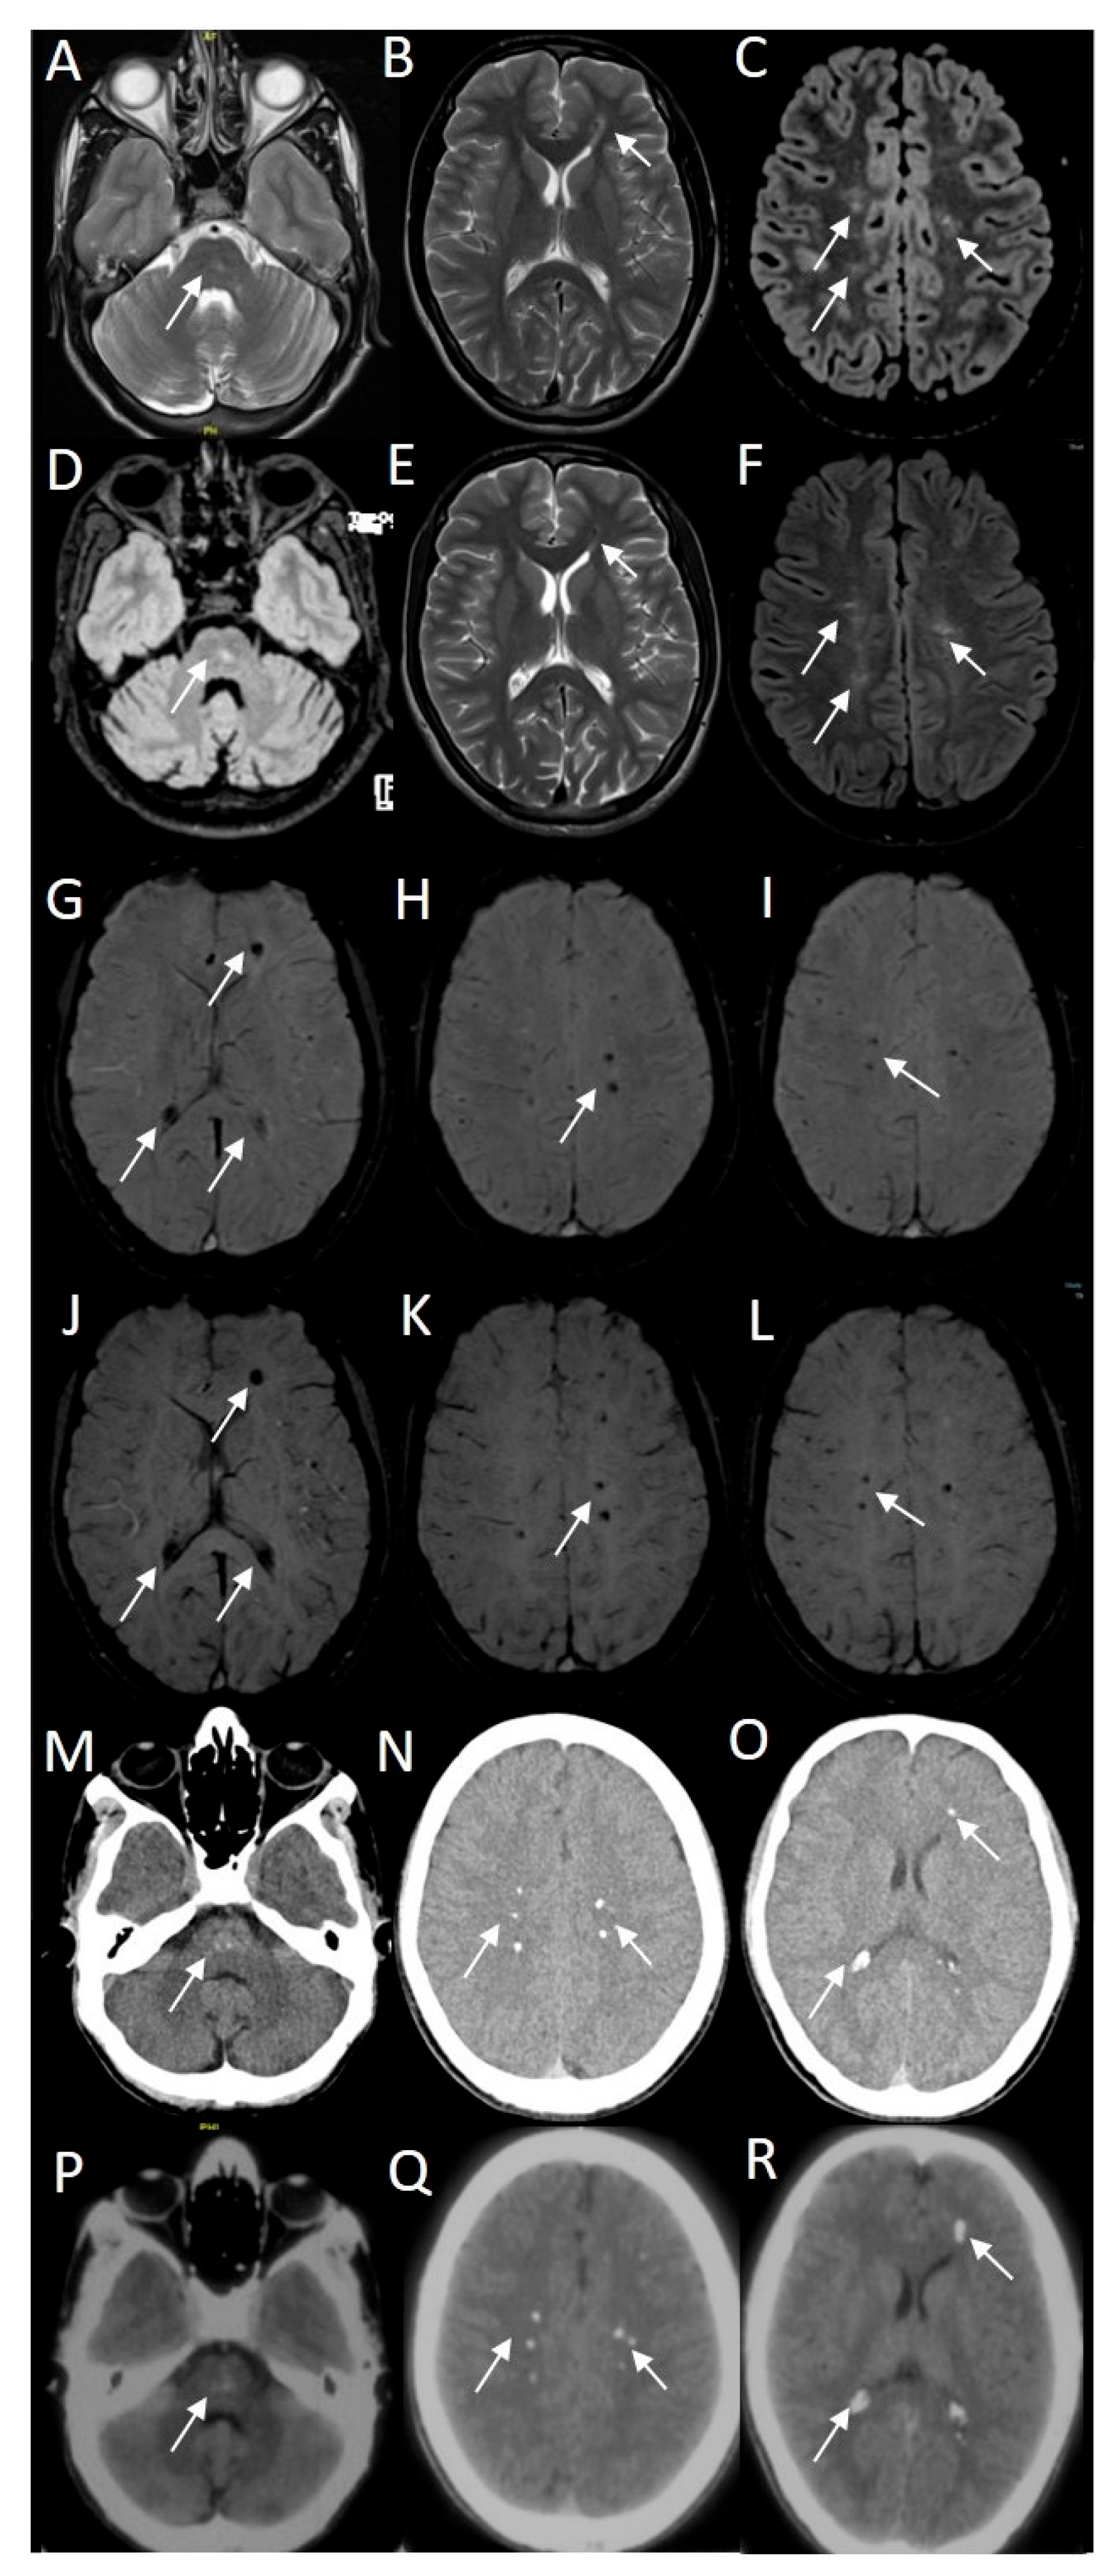

Asymmetric T2/FLAIR hyperintensities were seen using magnetic resonance imaging (MRI) in the pons, both centrum semiovale, and corona radiata (Figure 2). The same locations revealed punctate mineralization on susceptibility-weighted imaging (SWI) and curvilinear enhancement on contrast imaging. Magnetic resonance angiography (MRA) revealed the left vertebral artery terminating in posterior inferior cerebellar artery (PICA), along with evidence of a persistent left hypoglossal artery. The MRI spine screening was unremarkable. The CT brain images show punctate calcifications in the locations mentioned above, as well as in the pineal gland and bilateral choroid plexus.

Figure 2. Magnetic resonance imaging of the proband showed asymmetric hyperintensities in pons, bilateral centrum semiovale and deep white matter of the left frontal cortex (white arrows on T2/FLAIR axial images (AF)). Note that the MR images (AC) and (GI) were performed in April 2024, and images (DF) and (JK) were performed in June 2022. Susceptibility weighted imaging (SWI) showed punctate mineralization (white arrows on SWI axial images (GL)). CT brain images showed punctate calcifications in the pons, bilateral centrum semiovale, and deep white matter of the left frontal cortex (white arrows on CT images (MR)). Note that the CT images (MO) were performed in June 2022 and images (PR) were performed in September 2021.